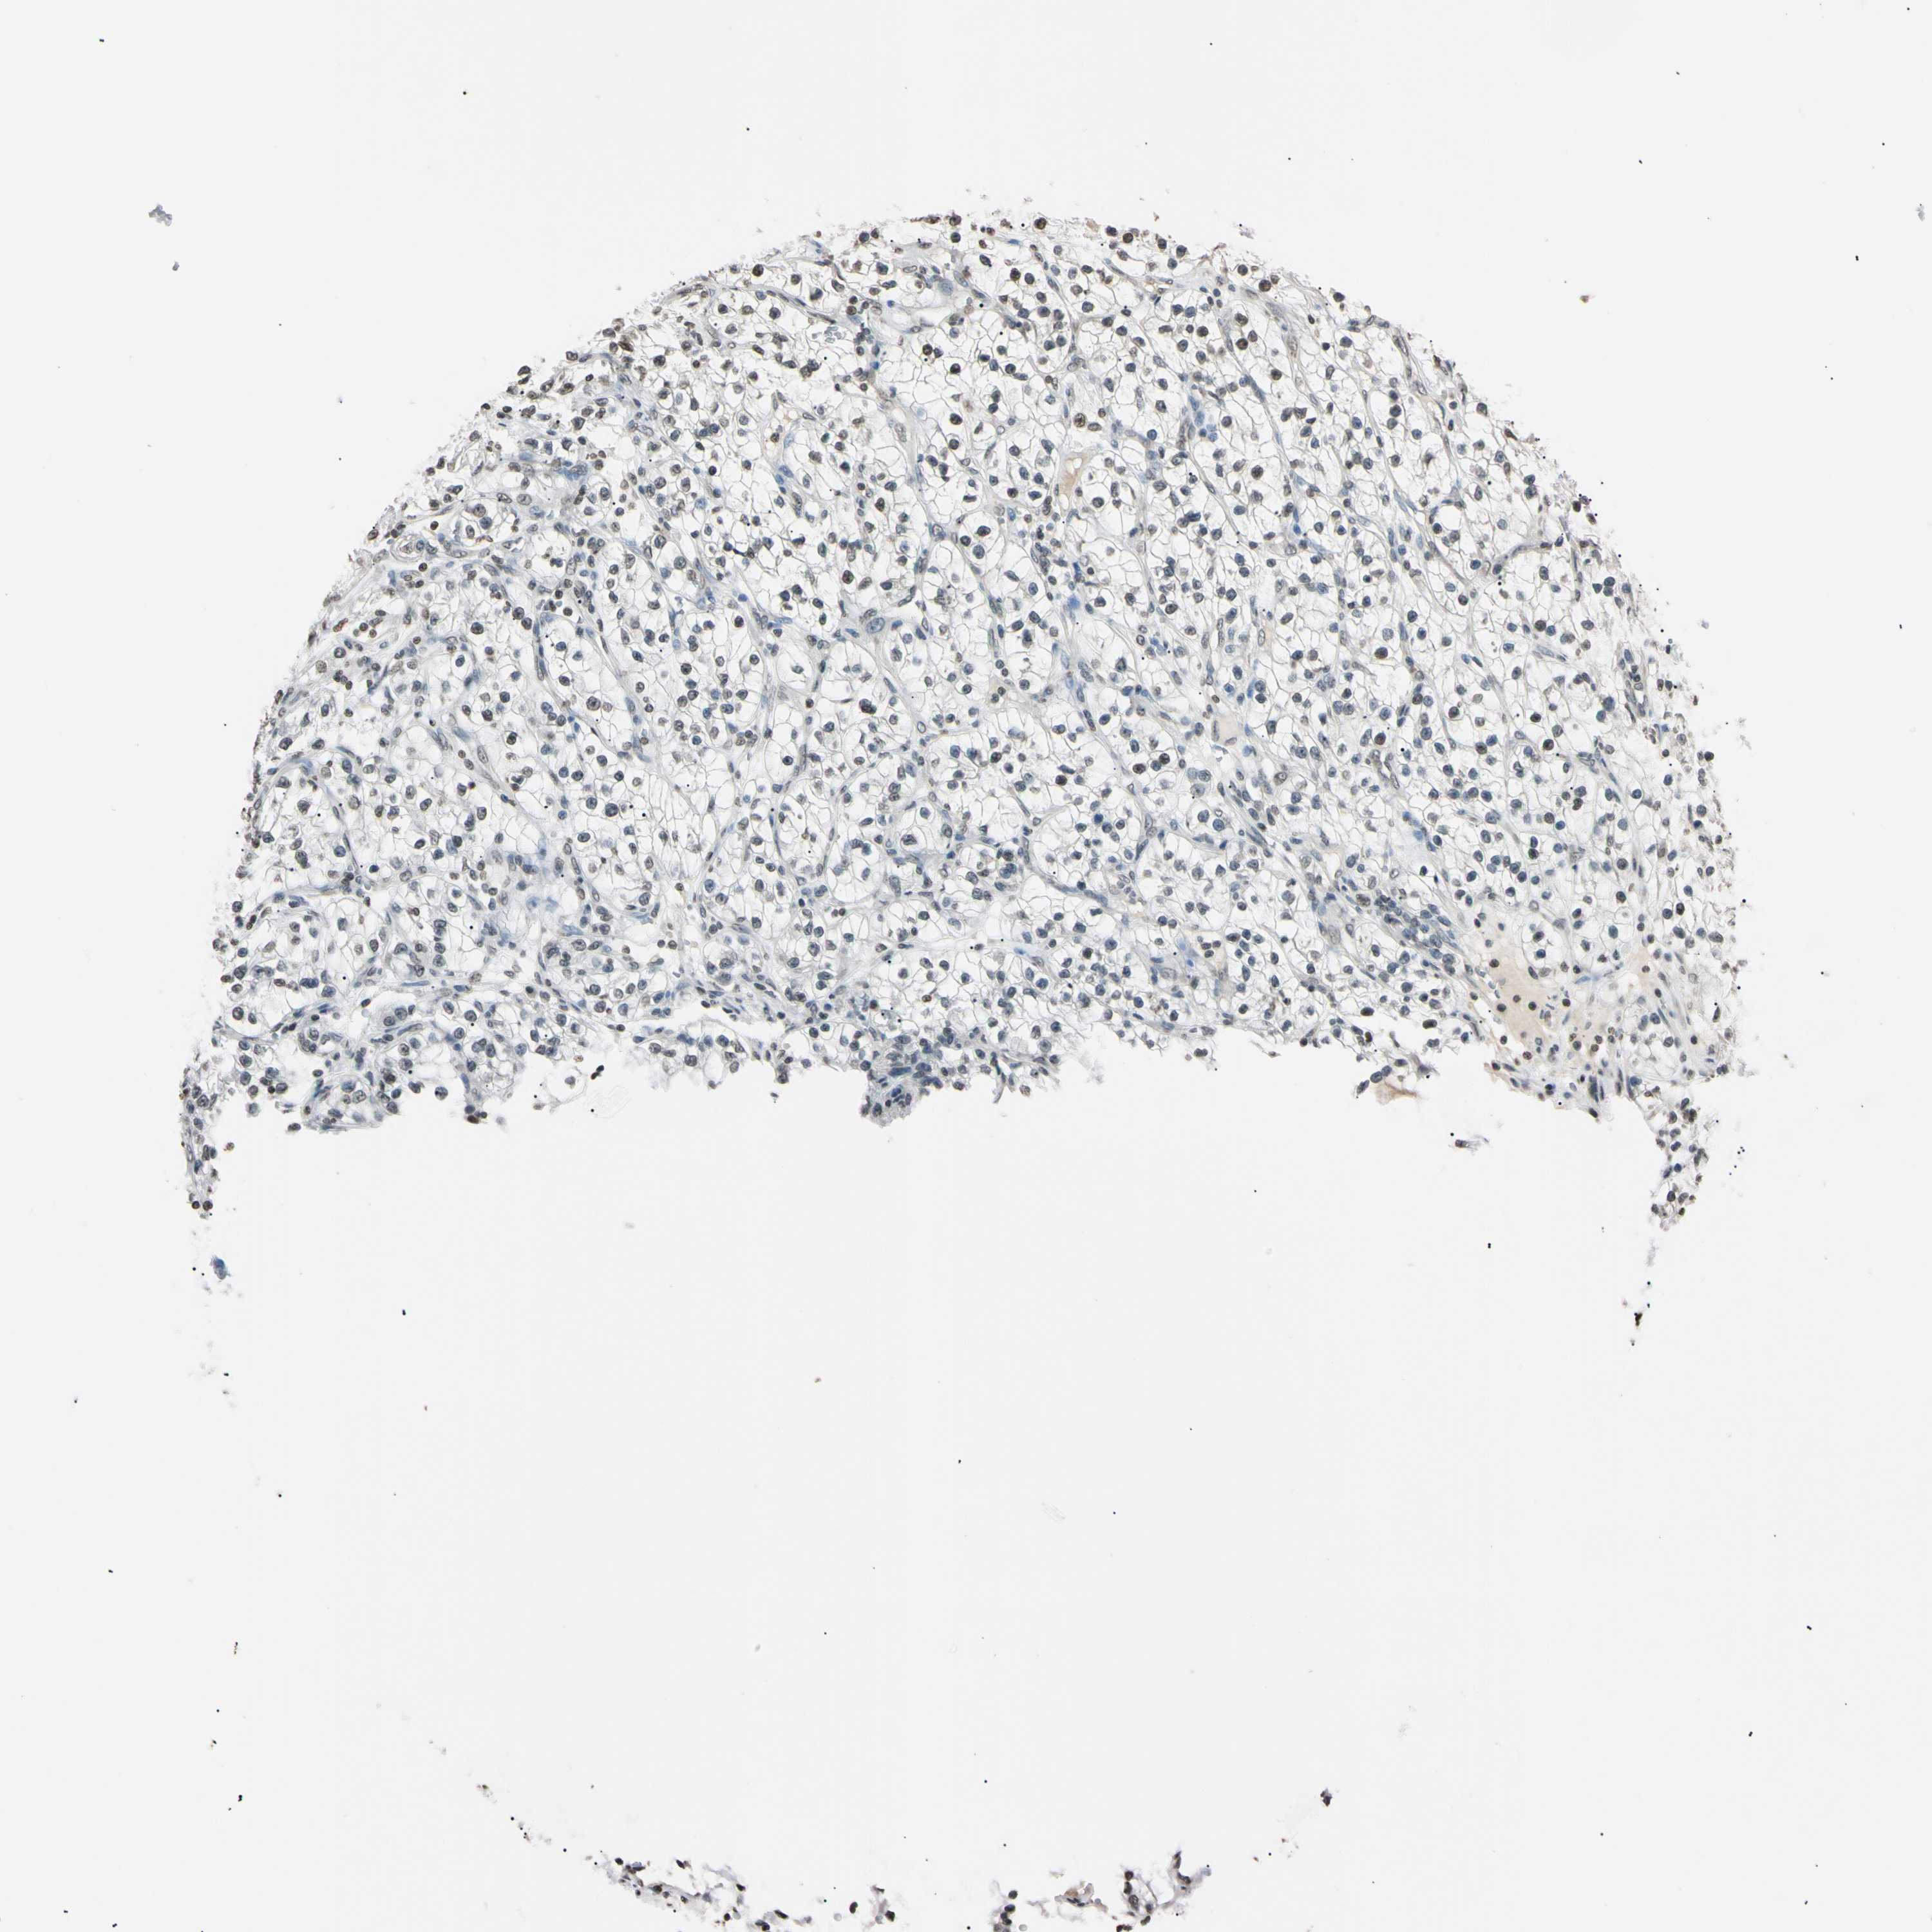

KIDNEY RENAL PAPILLARY CELL CARCINOMA (TCGA) - Interactive survival scatter ploti

The Survival Scatter plot shows the clinical status (i.e. dead or alive) for all individuals in the patient cohort, based on the same data that underlies the corresponding Kaplan-Meier plots. Patients that are alive at last time for follow-up are shown in blue and patients who have died during the study are shown in red.

The x-axis shows the expression levels (FPKM) of the investigated gene in the tumor tissue at the time of diagnosis. The y-axis shows the follow-up time after diagnosis (years). Both axes are complimented with kernel density curves demonstrating the data density over the axes. The top density plot shows the expression levels (FPKM) distribution among dead (red) and alive patients (blue). The right density plot shows the data density of the survived years of dead patients with high and low expression levels respectively, stratified using the cutoff indicated by the vertical dashed line through the Survival Scatter plot. This cutoff is automatically defined based on the FPKM cutoff that minimizes the p-score. The cutoff can be changed by dragging the vertical line or by entering a cutoff value in the square labeled "Current cut-off".

Under the Survival Scatter plot the p-score landscape (black curve; left axis) is shown together with dead median separation (red curve; right axis). Dead median separation is the difference in median mRNA expression between patients who have died with high and low expression, respectively. It is calculated as follows: median FPKM expression of dead patients with high expression - median FPKM expression of dead patients with low expression. This is intended to aid the user in visually exploring custom cutoffs and the associated p-scores and dead median separation.

Individual patient data is displayed and can be filtered by clicking on one or more of the category buttons on the top of the page. Categories describing expression level and patient information include: high, low, alive, dead, female, male and tumor stages. The scale of the x-axis can be toggled between linear and log-scale by clicking on the "x log" button. Mouse-over function shows TCGA ID, patient information and mRNA expression (FPKM) for each patient.

& Survival analysisi

Kaplan-Meier plots summarize results from analysis of correlation between mRNA expression level and patient survival. Patients were divided based on level of expression into one of the two groups "low" (under cut off) or "high" (over cut off). X-axis shows time for survival (years) and y-axis shows the probability of survival, where 1.0 corresponds to 100 percent.

CDC45 is potential prognostic, high expression is unfavorable in Kidney Renal Papillary Cell Carcinoma (TCGA)